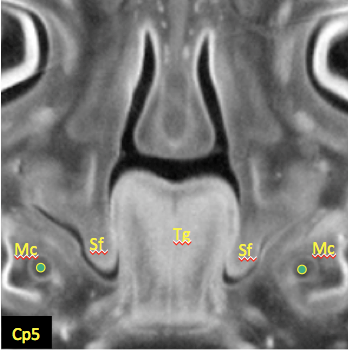

野原さんの修士論文がJ Anatに掲載

口蓋棚上昇前の数日間の下顎、舌が極度に前後に圧縮される時期を見出しました